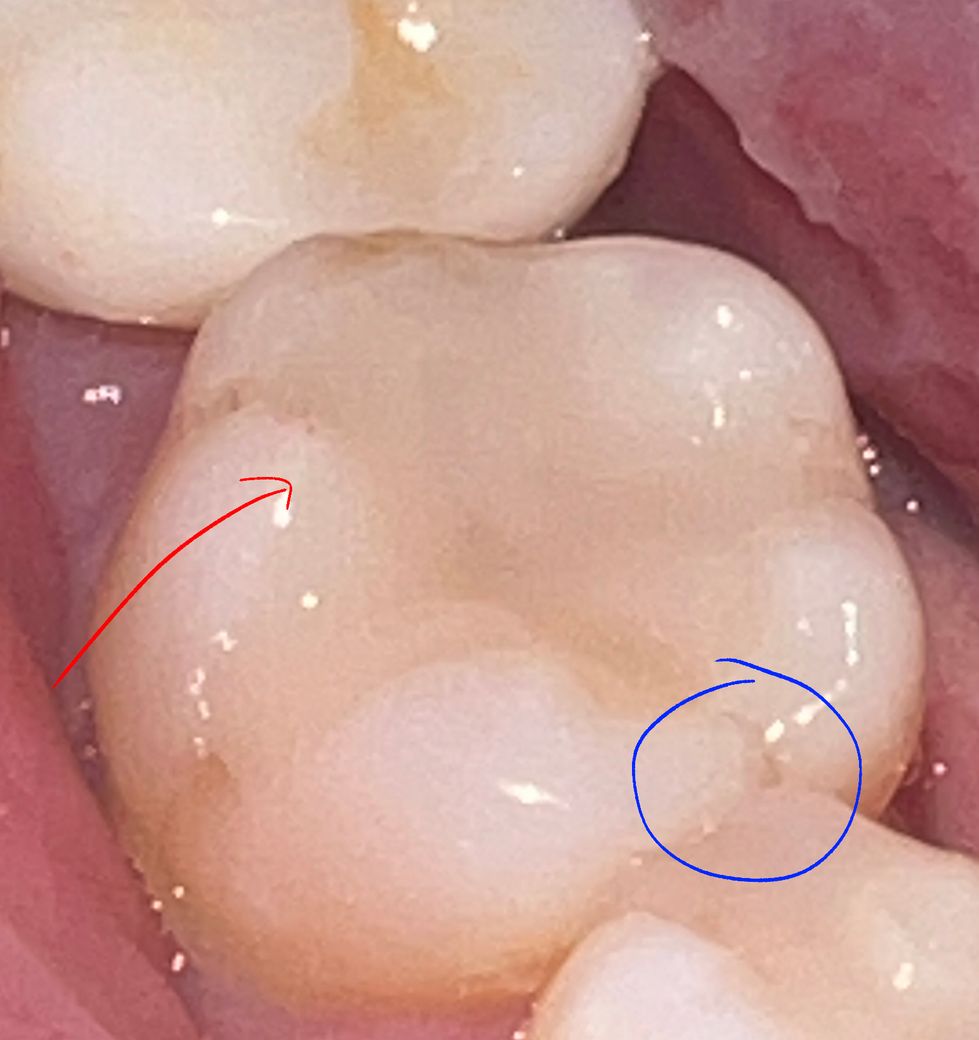

면봉으로 테스트 해봤을 때 한개의 치아 일부분(사진에서 붉은 화살표 친 부분)에서 찌릿한 통증이 있었는데요.

손으로 약간 힘을 줘서 눌러만 봤을 때도 찌릿한 통증이 있었구요.

큐레이 검사했을 때 금간 건 없다고 했는데 큐레이로 못 찾아내는 금도 있다고 하는데요.

금이 갔다면 면봉으로 테스트해 봤을 때 찌릿한 일부분에 금이 가죠? 사진에서 동그라미친 부분에 만약 금이 가있다고해도 붉은 화살표 친 부분이 아플 경우는 없는 거죠?

• 1번 째 사진